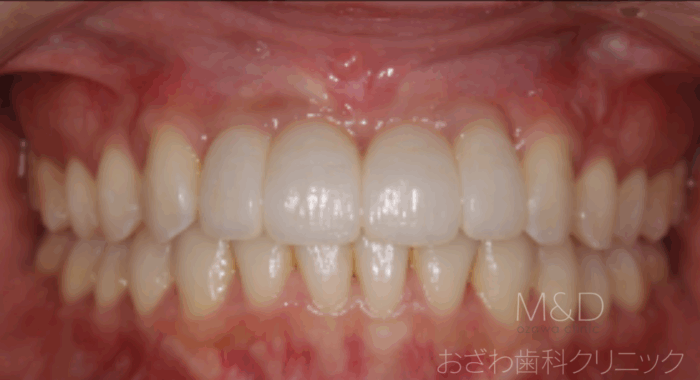

メリット

審美的で機能的な回復が行えます

ブリッジのように自分の健全な歯を削らなくて済みます

取り外しの入れ歯のようなわずらわしさや見た目の悪さがありません